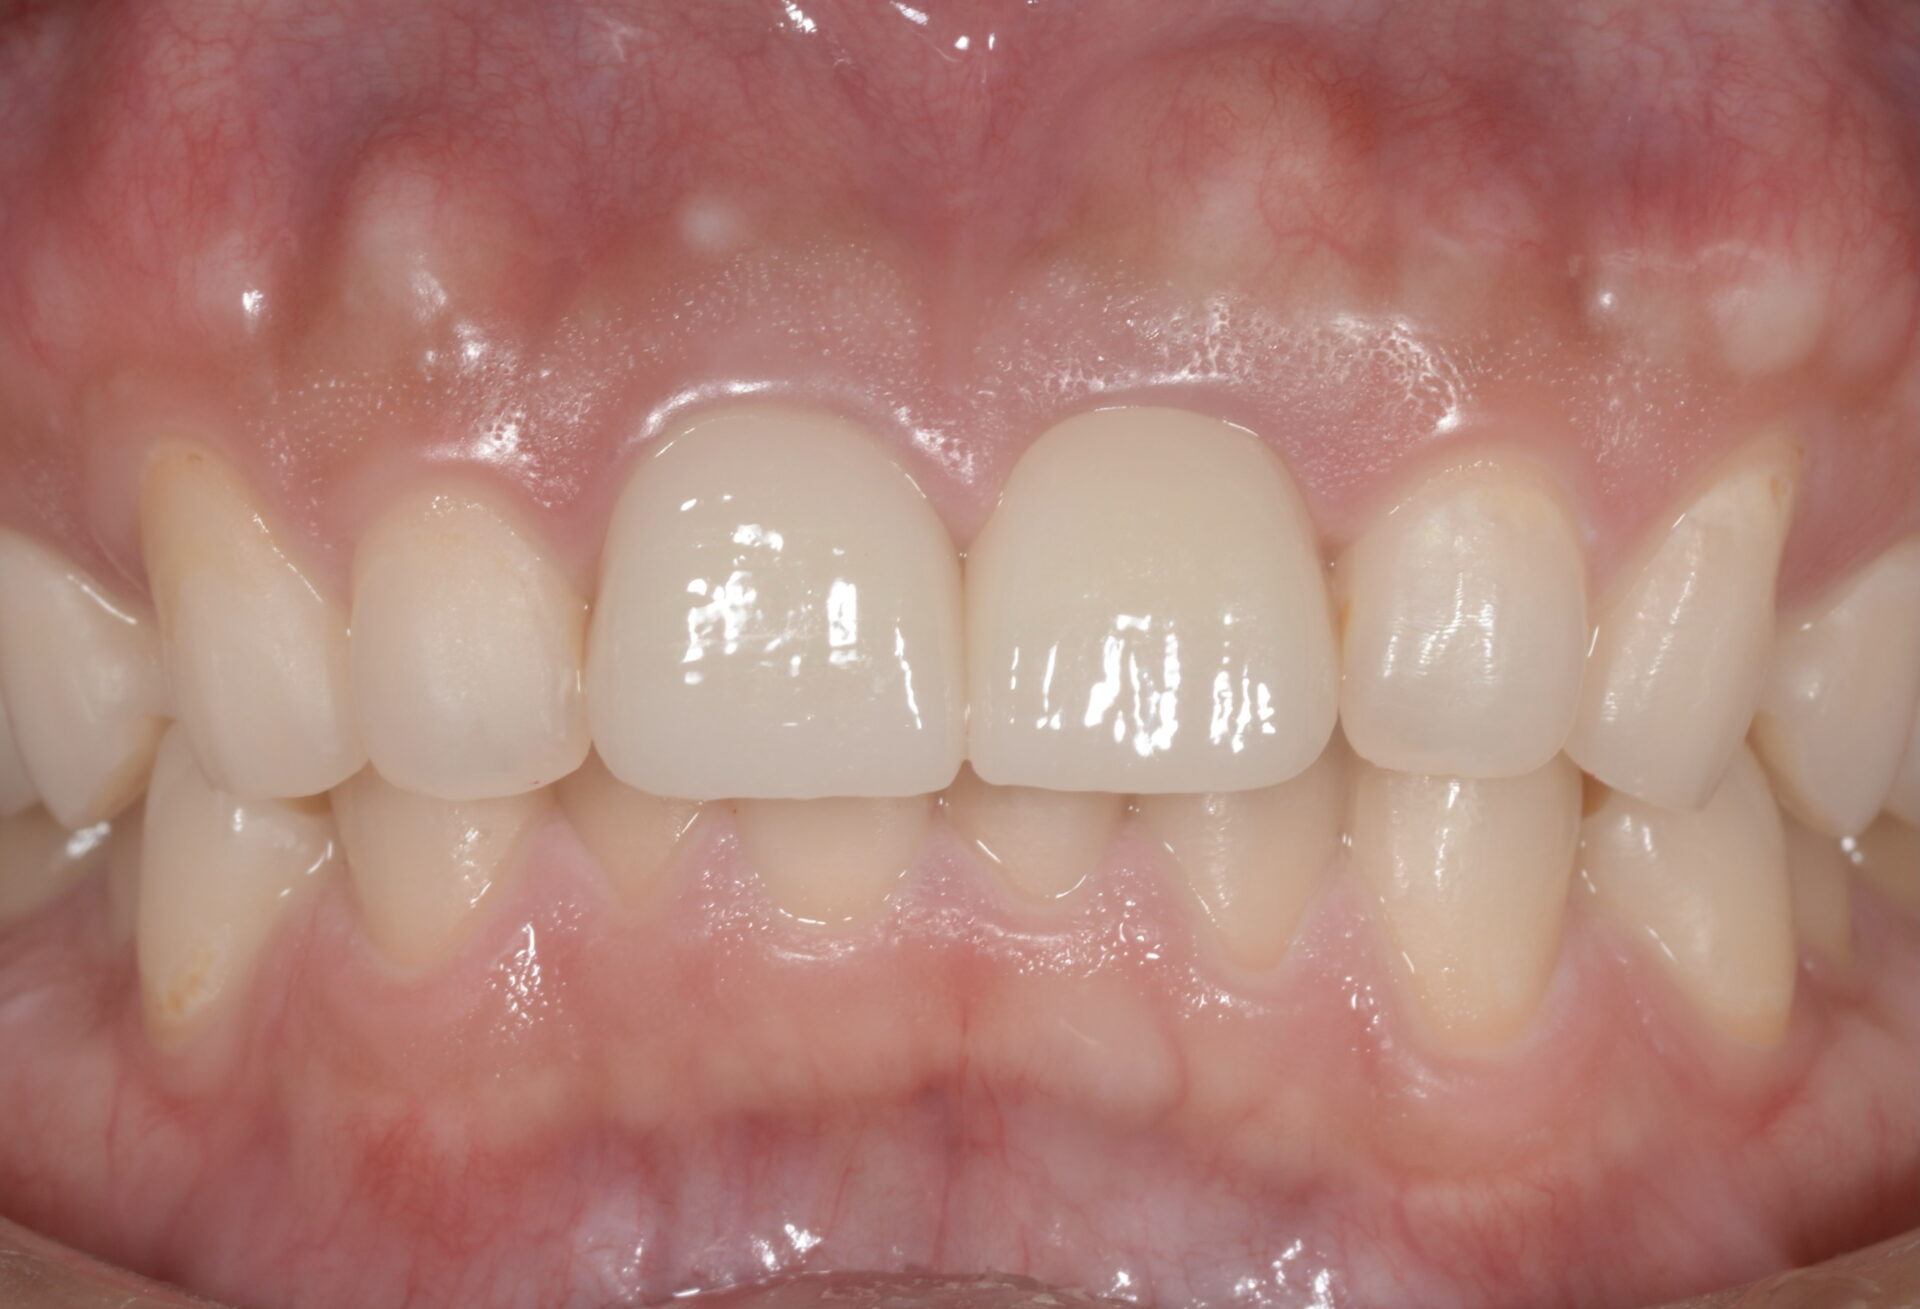

治療前後の写真です。ホワイトニングも行い、口腔内全体が明るい印象になりました。 レントゲンでは、右上顎中切歯の透過像は縮小しており、根尖性歯周炎は治癒傾向にあります。

患者様の熱心な口腔衛生環境の維持にも助けられ、スムーズな治療経過を辿ることができました。